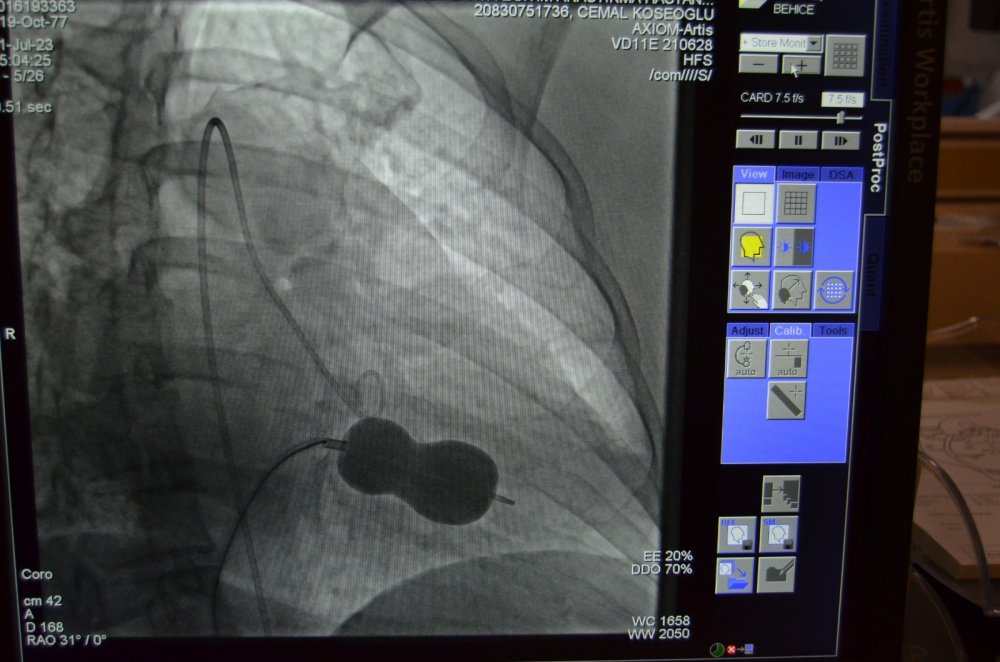

Alanya Eğitim ve Araştırma Hastanesi kardiyoloji ekibinden bir ilk. 45 yaşındaki hasta Behice Kanmaz, nefes darlığı ve çarpıntı şikâyetleri ile Alanya Eğitim ve Araştırma Hastanesi'nde görevli Alanya Alaaddin Keykubat Üniversitesi (ALKÜ) Tıp Fakültesi Öğretim Üyesi olan Kardiyoloji Uzmanı Doç. Dr. Cemal Köseoğlu'na başvurdu. Hastanede detaylı yapılan ön tetkik ve değerlendirmeler neticesinde Kanmaz’da romatizmal mitral darlığı ve kalbin sağ tarafında büyüme tespit edildi. Doç. Dr. Köseoğlu, kardiyoloji hekim arkadaşları ile hastanın durumunu değerlendirdi. Romatizmal kalp hastalığına bağlı mitral kapakta gelişen darlık ve mitral kapakta büyüme nedeniyle kardiyoloji hekimleri hasta Behice Kanmaz’ın mitral darlığının ameliyatsız tedavisine karar verdi.

Başarılı geçen girişimle ilgili açıklama yapan ALKÜ Tıp Fakültesi Öğretim Üyesi Doç. Dr. Cemal Köseoğlu, “Hastanemizde ilk kez uygulanan bu işlemi kardiyoloji birimi hekimleri olarak birlikte değerlendirdik ve mitral balon yardımıyla işlemi yapma kararı aldık. Hastamız Behice Hanımı, Anjıo Ünitemizde hiç uyutmadan mitral balon yardımıyla ile kasıktan girerek daralmış kapağını bir buçuk saat süren işlem sonunda açtık. Son kontrollerimizi yaptık. Hastanın kalp kapağı gayet güzel çalışıyor. 2 gün yoğun bakımda takibi sonunda taburcu işlemlerini gerçekleştireceğiz.” ifadelerini kullandı. Doç. Dr. Köseoğlu; Tıp teknolojisindeki gelişmeler ve giderek artan ameliyatsız müdahale olanakları ile çok ciddi kapak müdahalelerini çok düşük risklerle yapabilme olanağı bulduklarını da sözlerine ekledi.